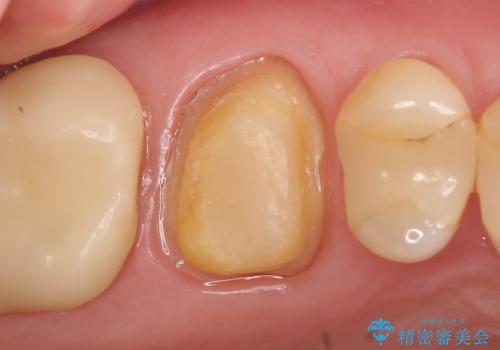

オールセラミッククラウン 根管治療後の補綴

- 他院にて右上6の神経が死んでいるため根管治療が必要だと言われ当院にいらっしゃった方の症例です。

X線上で根尖病変を認めたため根管治療を行い、その後オールセラミッククラウンによる補綴を行いました

- オールセラミッククラウン…¥100,000、仮歯…¥10,000、ファイバーコア…¥20,000費用は治療当時の料金となります